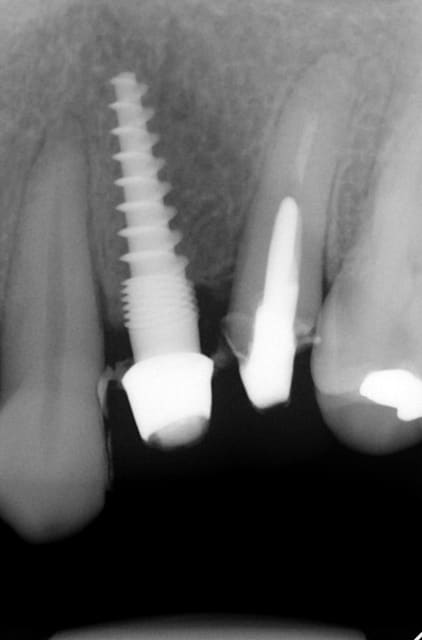

Bonjour flicflac je suis désolé de ma réponse tardive, oui il est vrai que ce n est pas beaucoup documenté ... je serai un menteur de dire que que je n ai jamais perdu des implants, surtout entre la 2eme et 8eme semaine après l implantation.Un échec vraiment à cause de la perte osseuse et avec le même process cela est arrivé une fois avec une madame, où l´os était encore infecté ( avant la chirurgie),mais après l ´échec (c était à la position 35) on a pu laisser le bridge. Malheureusement je n ai pas toutes les photos ici à Mallorque sur mon PC portable. Ci dessous une photo après 10 ans 46 47 et les implants au maxillaire.

attention exces de ciment distal 36....

Il semblerait que ces excès causerait d'emblé des péri-implantites selopn les paro.

Bonjour flicflac,

Oui ca semble ....sur la opg radio tu peux voir la situation seulement deux semaines après l´implantation immédiate 34 jusqu´à 36 et 45, les derniers 2 photos montrent la même situation après un an ( où on a enlevé la supra construction pour un contrôle). Sur ce cas je voulais montrer la bonne régénération osseuse et de la gencive.